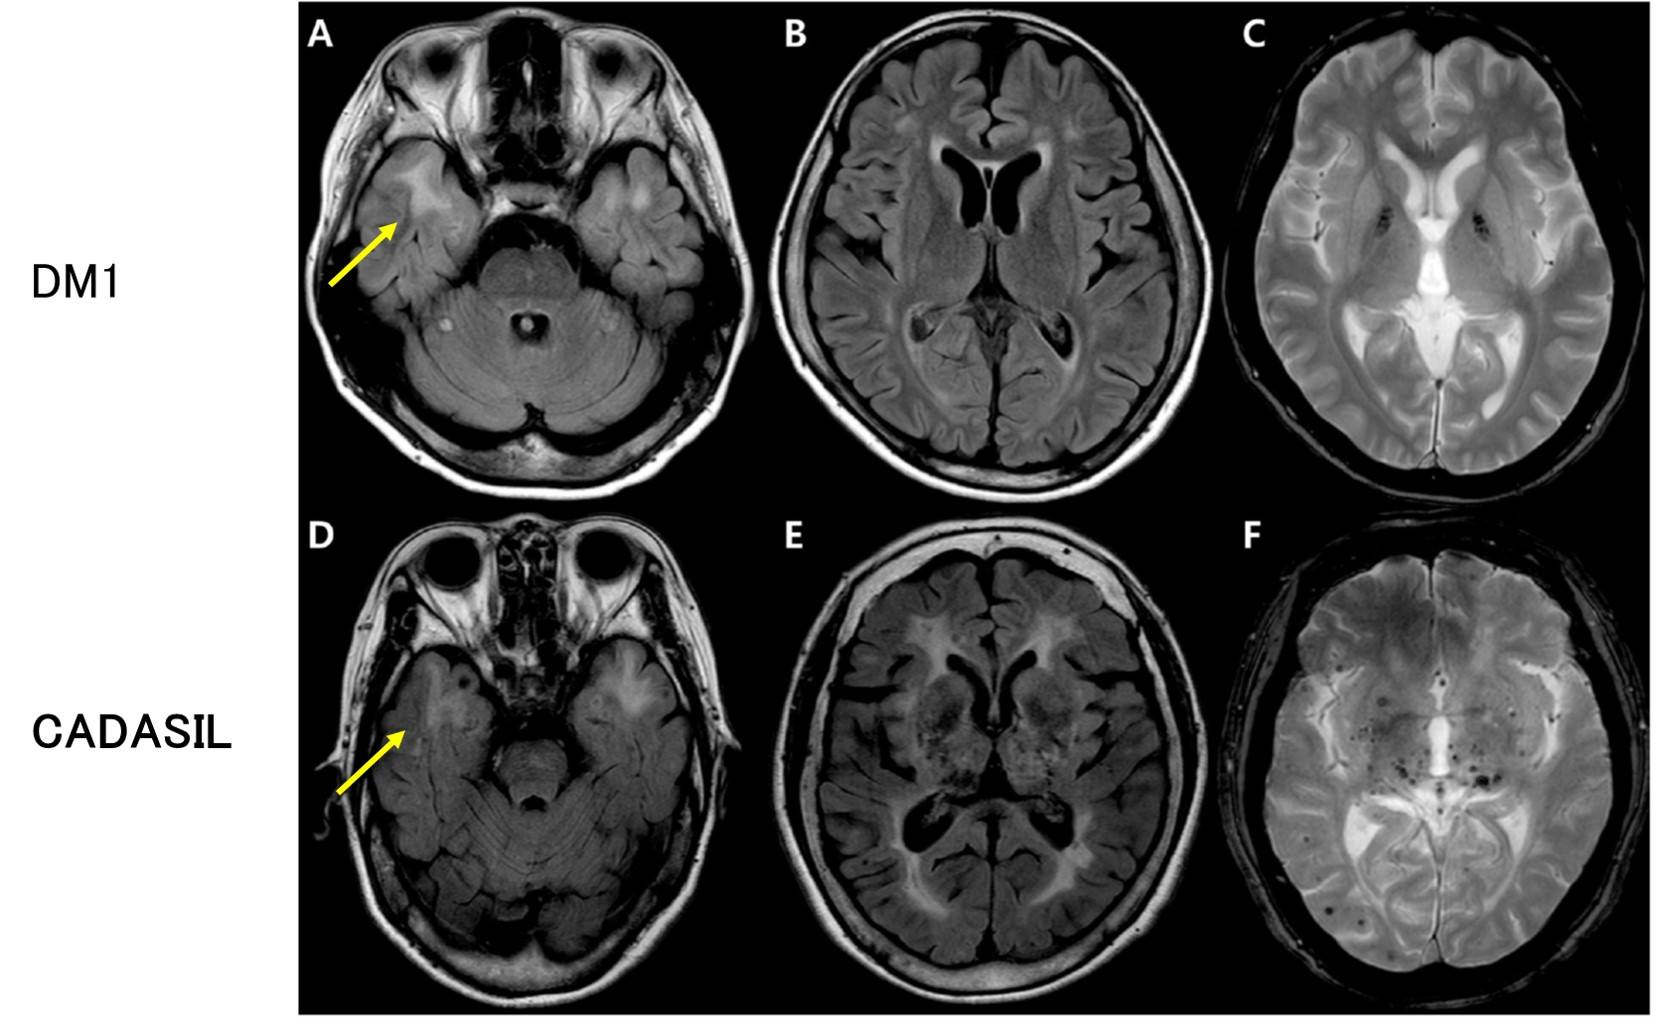

コラム | 岐阜大学大学院医学系研究科脳神経内科学分野, 脳血管の分子病態研究 | 研究紹介 - 新潟大学脳研究所 脳神経内科,

脳血管の分子病態研究 | 研究紹介 - 新潟大学脳研究所 脳神経内科, 朝倉書店『内科学』(第12版)デジタル付録,